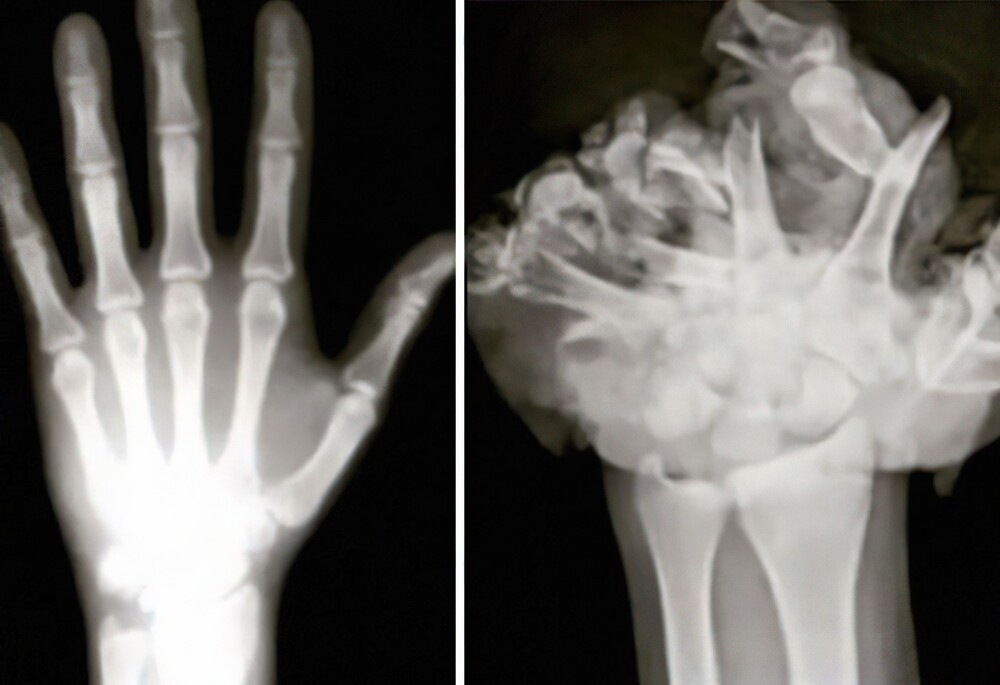

8. Normal hand/Hand after firework explosion